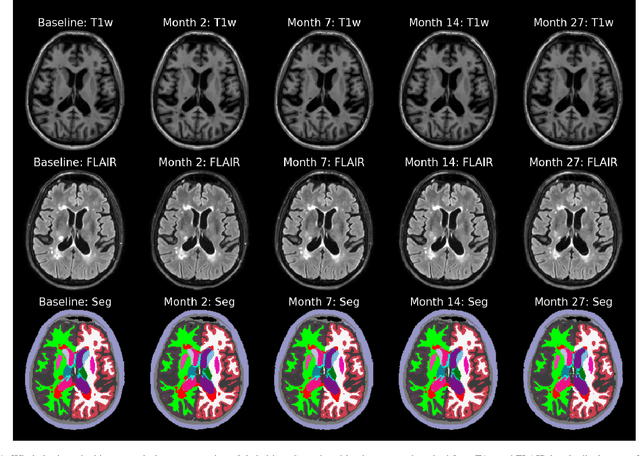

Abstract:In this paper we describe and validate a longitudinal method for whole-brain segmentation of longitudinal MRI scans. It builds upon an existing whole-brain segmentation method that can handle multi-contrast data and robustly analyze images with white matter lesions. This method is here extended with subject-specific latent variables that encourage temporal consistency between its segmentation results, enabling it to better track subtle morphological changes in dozens of neuroanatomical structures and white matter lesions. We validate the proposed method on multiple datasets of control subjects and patients suffering from Alzheimer's disease and multiple sclerosis, and compare its results against those obtained with its original cross-sectional formulation and two benchmark longitudinal methods. The results indicate that the method attains a higher test-retest reliability, while being more sensitive to longitudinal disease effect differences between patient groups. An implementation is publicly available as part of the open-source neuroimaging package FreeSurfer.